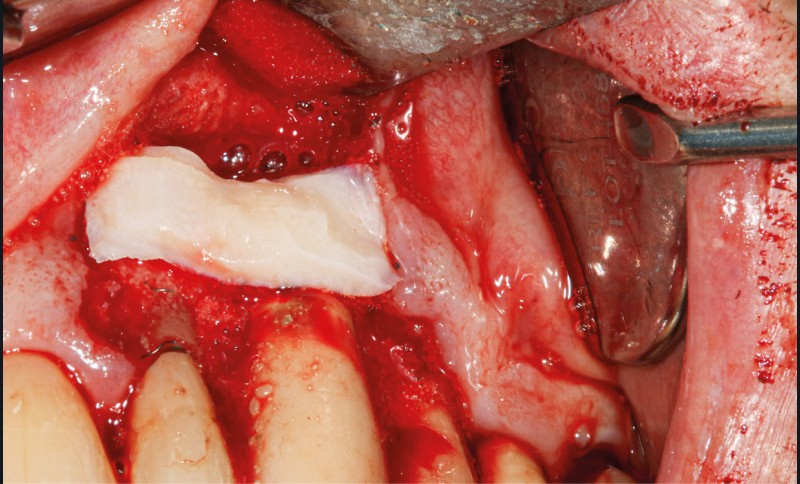

– Le laser Er-YAG, utilisé pour le nettoyage, est un laser avec un milieu actif composé d’yttrium, d’aluminium et de grenat dopé à l’erbium. Avec une longueur d’onde de 2 940 nm situé dans l’infrarouge, le laser Er-YAG est un laser à haute énergie, dont la lumière est absorbée dans l’eau et dans l’hydroxyapatite et qui ne pénètre pas profondément. Ceci permet de couper des tissus mous et des tissus durs, mais également de désorganiser le biofilm bactérie.

C’est un laser idéal pour le traitement chirurgical des péri-implantites. Il permet l’élimination du tissu de granulation à la surface de l’implant et de l’os ainsi qu’une décontamination mécanique par effet photoablatif.– Le laser Diode, utilisé pour la décontamination…